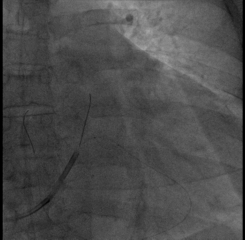

AP

LAO45

RAO30

固定左室电极,连接CRTD(DTBC2QQ),手术最终影像

在缝合过程中即由工程师进行无线测试(可不通过程控探头探寻)

如上图,通过Vector Express功能很快自动测试四极多向量的阈值供参考,选择LV2-LV3向量,该向量阈值最低,预估寿命最长

心房、右室、左室的其它参数也均满意

经过术后即可优化,QRS宽度即刻缩窄!预示患者良好的预后。